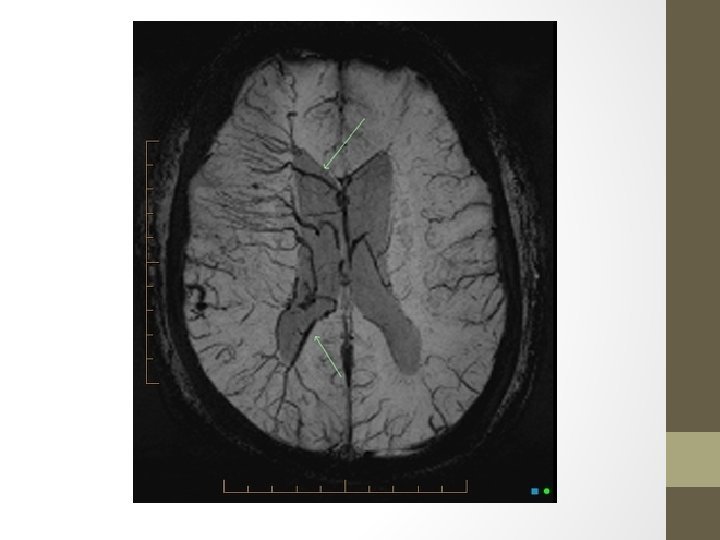

Vein Of Galen • Formed by the union of the two internal cerebral veins and basal veins of Rosenthal • Drain into the confluence of the inferior sagittal sinus and the anterior extremity of the straight sinus

Vein Of Galen Malformation • The most frequent arteriovenous malformation in neonates. • Results from an aneurysmal malformation with an arteriovenous shunting of blood • Develops during weeks 6 -11 of fetal development as a persistent embryonic prosencephalic vein of Markowski • Typically result in high-output congestive heart failure or may present with developmental delay, hydrocephalus, and seizures. (vary with the type of malformation) • Has been associated with capillary malformationarteriovenous malformation (CM-AVM), which is a newly recognized autosomal dominant disorder, caused by mutations in the RASA 1 gene in 6 families

• Presentation commonly with high output cardiac failure in neonates while mostly hydrocephalus in infants and children • Angiography: gold std • Classification - Lasjaunias classification: Ø Choroidal: tend to present earlier (neonate) with more severe shunts&high output cardiac failure Ø Mural: present later (infant) and typically with hydrocephalus. Fewer fistulas-high outflow restriction -Yasargil Classification Ø type I: small pure cisternal fistula between the vein of Galen and either the pericallosal arteries (anterior or posterior) or posterior cerebral artery Ø type II: multiple fistulous communications between the vein of Galen and the thalamoperforating vessels Ø type III: high flow mixed type I and II Ø type IV: parenchymal arteriovenous malformation (AVM) with drainage into the vein of Galen

Tx&Prognosis • Arterial feeder and fistula occlusion • Transtorcular or transvenous embolisation of the dilated vein • Prognosis is largely determined by the presence or absence of cardiac failure. Thus choroidal types and those presenting in the neonatal period do poorly.